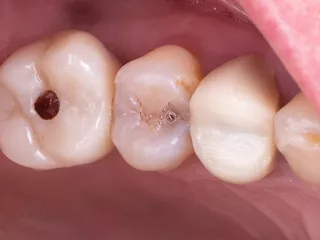

1. Pre-operative clinical view

The occlusal view shows a ridge with a satisfactory width and a thick, healthy periodontal phenotype.